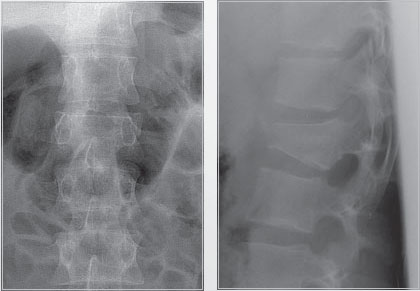

Мужчина, 22 года, саркома Юинга (Ewing's sarcoma). Корпэктомия с замещением тела имплантом Obelisc, фиксация транспедикулярной системой